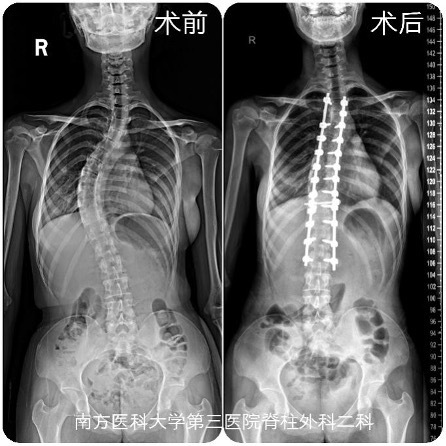

脊柱侧弯让少女的背部拱成了剃刀的形状,还越来越痛,影响行走运动。近日,广州南方医科大学第三附属医院(简称“南医三院”)脊柱外科黎庆初教授为17岁的达娃实施了矫正手术,终于让她挺起了脊梁,恢复了健康。

入院后,南医三院脊柱外科二科主任黎庆初经过详细检查评估,建议手术纠正达娃的“剃刀背”。脊柱侧弯畸形矫术手术难度大、出血多,而患者较瘦,体重指数(BMI)只有19,且还有中度贫血,手术风险较大。黎庆初团队经过详细讨论,慎重制定达娃的手术方案。完善术前准备后,黎庆初于8月31日为达娃行脊柱侧弯畸形矫正术,手术过程顺利。术后第五天,达娃佩戴支具下床活动,术前身高162厘米,术后“长高”了5厘米。